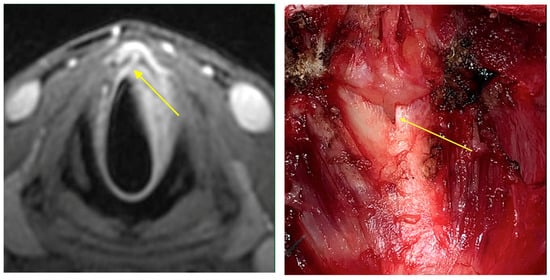

Intraoperative endoscopy allowed for a thorough reassessment of the tumor extension and highlighted some clinical-endoscopic elements of suspected initial extra laryngeal extension (Figure 1 and Figure 2).

Figure 2. The radiological finding of suspected extra laryngeal extension through the cricothyroid membrane is evidenced (yellow arrow). Intraoperative evaluation (yellow arrow) confirmed the extra laryngeal spread through a vascular foramen of the cricothyroid membrane.